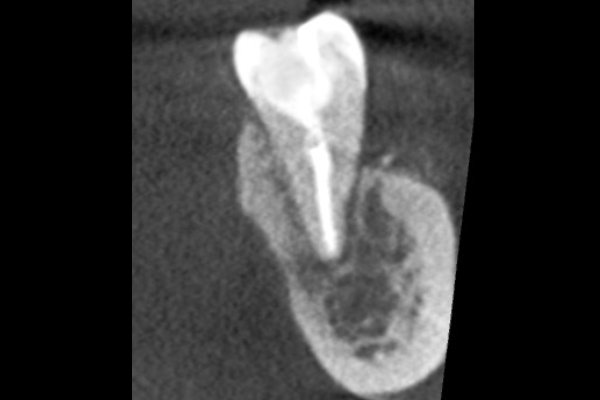

30代女性の前歯部の症例

- 主訴

- 「前歯で咬むと違和感がある」とのことでご来院されました。数週間前から症状があり、他の医院では「抜歯の可能性がある」と言われ、不安に感じていらっしゃいました。

- 期間

- 治療期間2ヶ月、治療回数3回、レントゲン写真で治癒を確認できるまでの期間6ヶ月

- 治療内容

- 1.古い被せ物の除去と虫歯の徹底除去

まず、古い銀歯を外し、内部に広がっていた虫歯を丁寧に取り除きました。

2.マイクロスコープ下での根管治療

唾液などによる細菌の侵入を防ぐ「ラバーダム」を装着し、マイクロスコープ(歯科用顕微鏡)で根管内を数十倍に拡大しながら治療を進めました。複雑な形状の根管の内部まで、汚染された組織を徹底的に洗浄・消毒します。

3.根管充填(こんかんじゅうてん)

根管内が完全にクリーンになったことを確認し、再感染を防ぐために専用の薬剤で隙間なく密閉しました。

4.土台と被せ物の作製

歯の強度を補うための土台を立て、最終的なセラミックの被せ物を作製し、装着しました。

- 治療に伴うリスク

- 少しでも汚染物質が残ると再発のリスクが高まります。